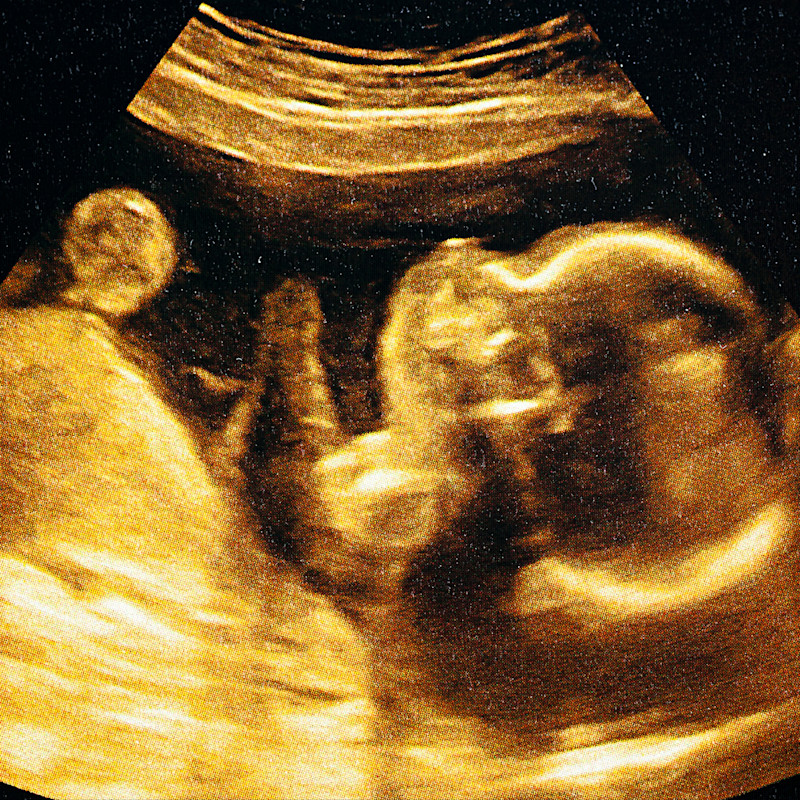

Halfway through pregnancy, Katy Preidt and Dustin Lower received the news that their baby had a tumour growing on his neck. Immediate concerns were raised, as doctors feared that, once delivered, the tumour would block the infant's airway.

Cervical teratomas are often detected prenatally during routine ultrasounds, typically around 18 weeks of gestation.

The tumours appear as large, asymmetric, and well-demarcated masses, often with solid and cystic components. Polyhydramnios, or excess amniotic fluid, may be present due to oesophageal compression, leading to swallowing difficulties.